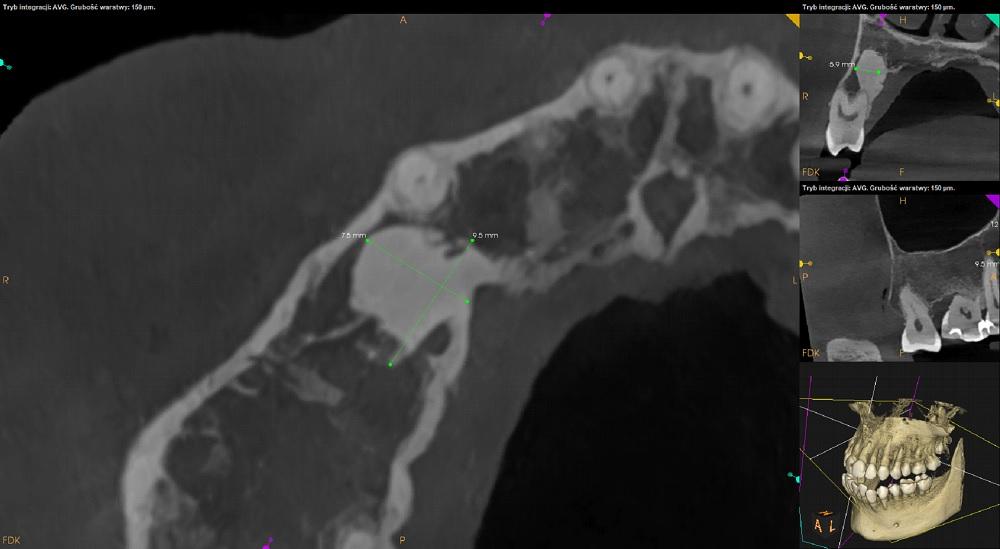

Wokół korzenia podniebiennego zęba 14 rozległe ognisko osteosklerotyczne (około 12,5mm x 9,5mm x 7,5mm) zlewające się z blaszką zbitą po stronie podniebiennej.

Widoczna resorpcja korzenia podniebiennego.

Obraz radiologiczny może odpowiadać dysplazji cementowo-kostnej.